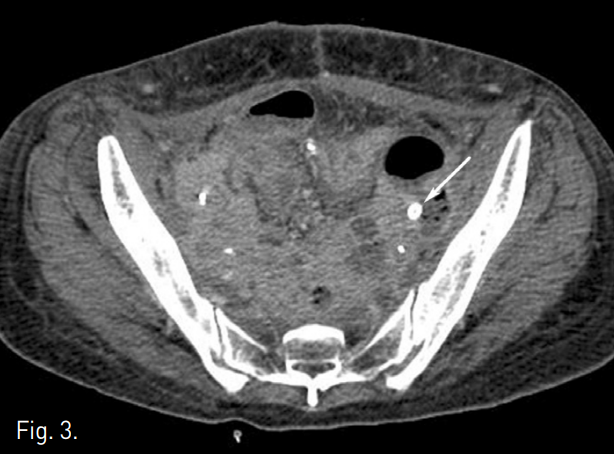

초음파 유도하에 우총대퇴동맥을 천자하여 5F sheath를 삽입하고 시행한 골반동맥조영술에서 양측 장골동맥이 매우 가늘어져 있으며, 좌측 외장골동맥에서의 혈관외 유출이 관찰되었다(Fig. 2A). 4mm × 2cm Savvy(Cordis, Miami Lakes, FL, USA) 풍선카테터를 이용하여 임시로 천공부위를 막았다(Fig. 2B). 저혈량증에 의해 장골동맥이 매우 가늘어져 있어서 굵은 sheath를 넣고, 자가팽창 성 stent-graft 설치하기에는 어려움이 있을 것으로 생각하고, 좌측 총대퇴동맥을 천자하여 7F sheath를 삽입한 뒤 4~9mm × 28mm Jo stent-graft(Abbott lab. vascular enterprise Ltd., Beringen, Switzerland)를 5mm × 4cm P3 balloon catheter에 거치시켜서 천공부위에 설치하였다(Fig. 2C). 한달 뒤 시행한 조영증강 골반 CT에서 출혈의 증거는 없었다(Fig. 3).

A follow-up CT obtained 10 days after stent-graft placement shows complete exclusion of the pseudoaneurysm and good patency of left external iliac artery (arrow).